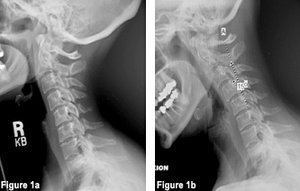

As reported by our radiologist, the radiographs demonstrated straightening of the normal cervical curvature, posterior osteophytes on the left at C4-5, C5-6, C6-7. There was also flexion subluxations note C2 on C3, C3 on C4, C4 on C5 with 15-degree flexion instability at C4-5 during flexion with overpressure (Figures 1a and 1b).